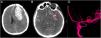

Hinged craniotomy (HC) is an alternative surgical technique that can be used in place of decompressive craniectomy (DC) to treat refractory intracranial hypertension. This procedure has the advantage of avoiding the need for a second surgery to replace the bone, while giving a good control of intracranial pressure. However, there is no consistent literature about complications of HC. In particular, there are no reported cases of contralateral subdural effusion (CSE) after HC. In this article we present a case of a 55-years-old man who developed CSE after a hinged craniotomy (HC) for intracranial hypertension, and how we handled it. Therefore, we explored literature to better understand the pathogenesis of CSE, treatments and possible prevention strategies.